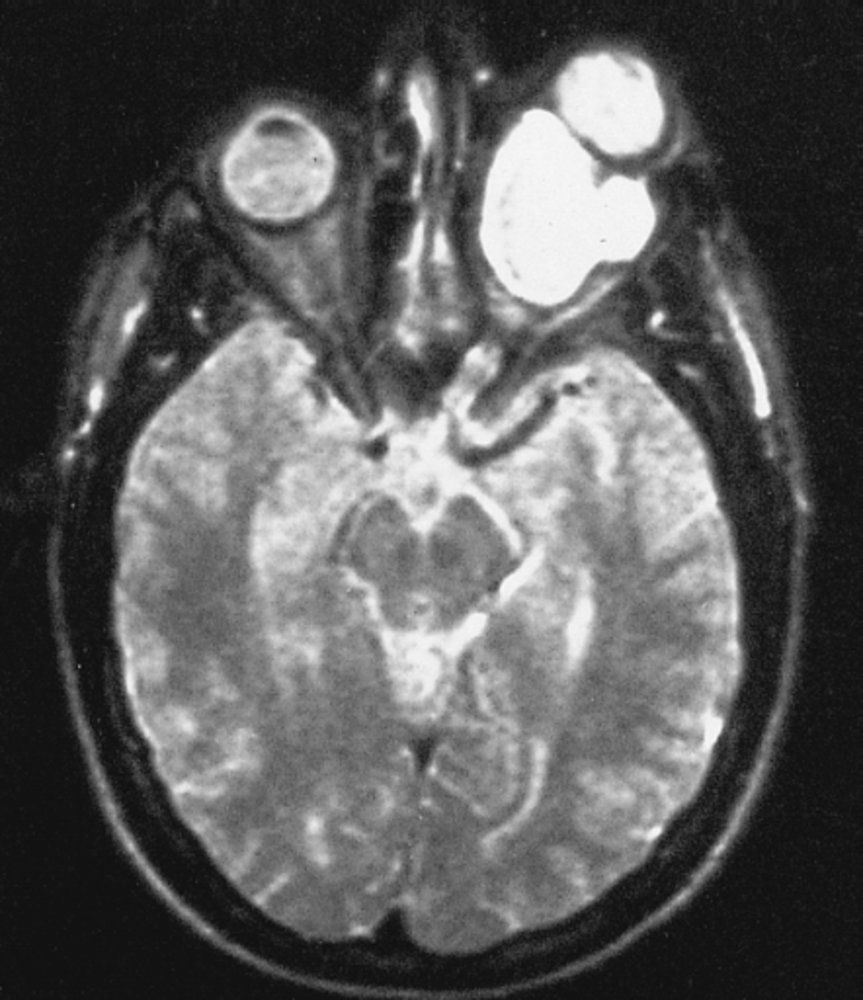

- Imaging: MRI head and brainstem with IV contrast (to assess for, e.g., vestibular schwannoma, multiple sclerosis, TIA) [17][48]